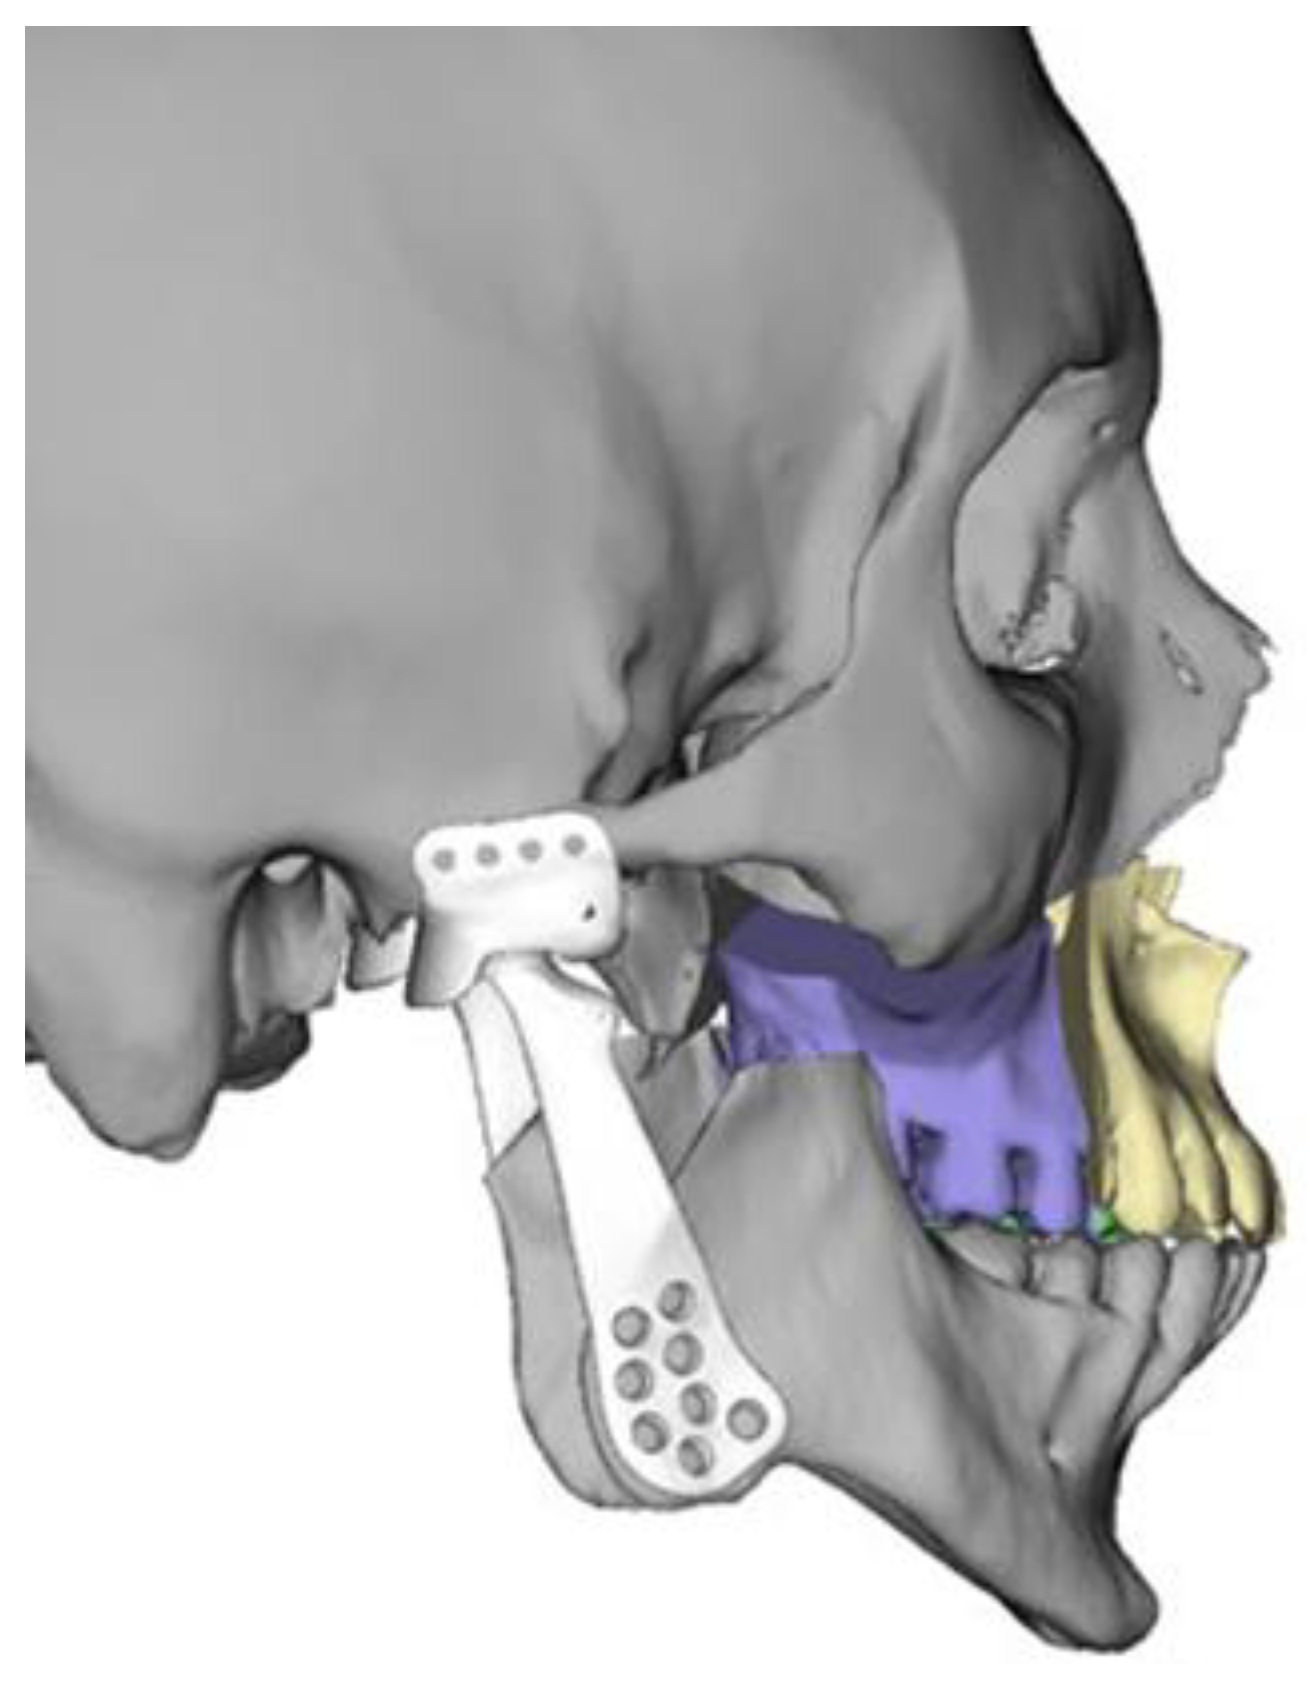

2.2. Virtual Surgical Planning and Computer-Aided Manufacturing Workflow

2.3. Surgical Technique

2.3.1. Mandible

2.3.2. Maxilla